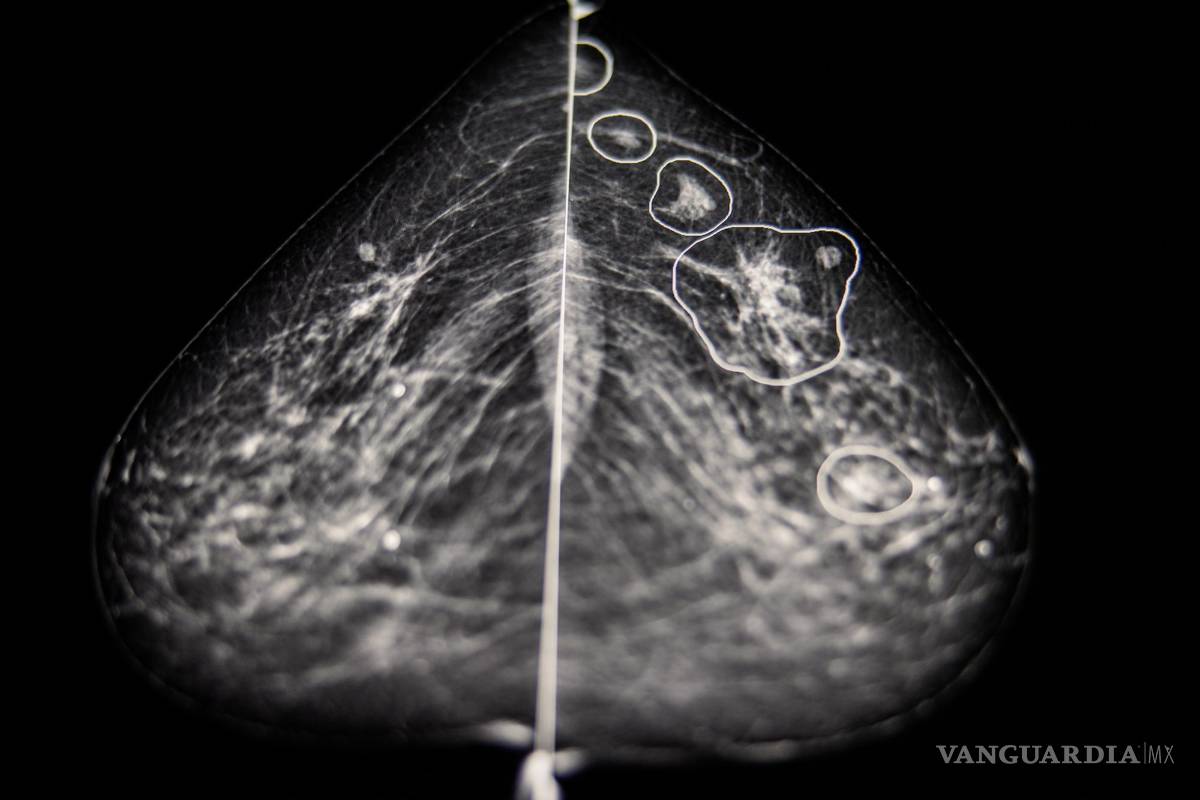

En el interior de una habitación oscura del Hospital del Condado de Bács-Kiskun en la periferia de Budapest, Éva Ambrózay, una radióloga con más de veinte años de experiencia, observaba un monitor de computadora que mostraba la mamografía de una paciente.

Dos radiólogos ya habían dicho que la radiografía no mostraba ningún signo de que la paciente tuviera cáncer de mama. Pero Ambrózay observaba atentamente varias zonas del escáner marcadas en rojo, que el programa de inteligencia artificial había señalado como potencialmente cancerosas.

A partir de los millones de casos que recibe el sistema, la tecnología crea una representación matemática de las mamografías normales y las que presentan cáncer. Gracias a su capacidad para analizar cada imagen de manera más detallada que el ojo humano, compara esa referencia para detectar anomalías en cada mamografía.

El año pasado, después de hacer pruebas con más de 275 mil casos de cáncer de seno, Kheiron informó que su programa de inteligencia artificial igualaba el desempeño de los radiólogos humanos cuando se usaba para una segunda interpretación. Además, reducía la carga de trabajo de los radiólogos en al menos un 30 por ciento, ya que disminuía el número de radiografías que tenían que leer. En otros resultados obtenidos el año pasado en una clínica húngara, la tecnología aumentó la tasa de detección de cáncer en un 13 por ciento porque se identificaron más tumores malignos.

En el Hospital del Condado de Bács-Kiskun en la periferia de Budapest, Ambrózay comentó que al principio dudó de la tecnología, pero se convenció muy poco tiempo después. Mostró la radiografía de una mujer de 58 años con un pequeño tumor detectado por la inteligencia artificial que a Ambrózay le costaba ver.

Esta tecnología identificó algo, dijo, “que pareció salir de la nada”.